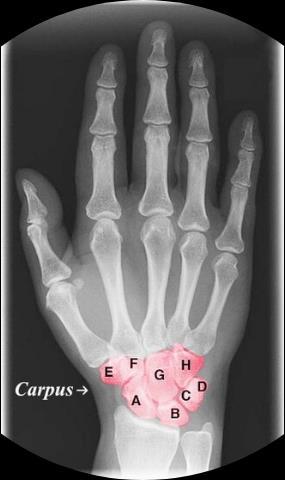

成人骨骼總數 成人身體由多達兩百多塊

大小不一的骨骼組成。每一塊骨頭

都有它的名字和專屬任務喔!